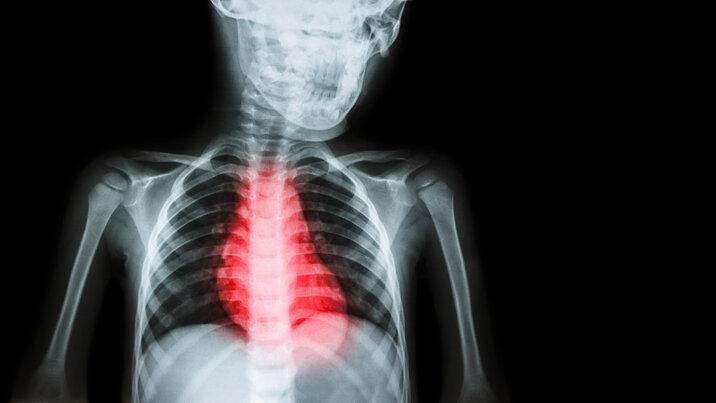

医生在做CT影像检查时发现 , 她的左肺里面的组织已经被结核菌“吃”掉了 , 形成了巨大的空洞 , 空洞里有脓液 。

▲右边空白部分就是被细菌“吃”掉的

医生告诉采访人员 , 结核分枝杆菌不仅伤肺 , 还会“吃掉”肺脏 。 正常情况下 , 肺部充满气体 , 做CT时应该是黑色透亮的 。 但罹患肺结核后的患者 , 肺部CT影像会出现空洞及肺组织纤维化收缩 , 像被“吃掉”了一样 。